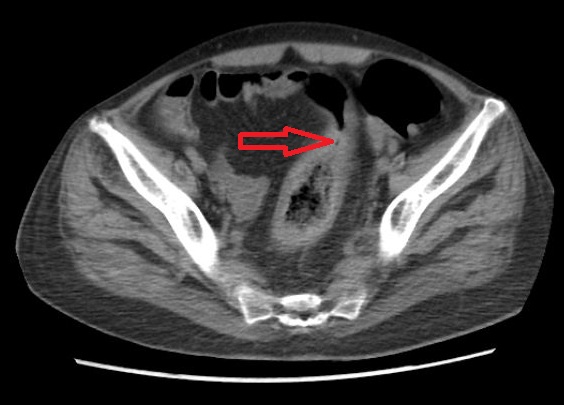

Ogilvie’s syndrome or acute colonic pseudo-obstruction is a rare and acquired disorder characterized by significant dilatation of the colon. The condition is mainly seen in hospitalized patients with medical or surgical problems. We report the case of a middle aged healthy lady who presented with Ogilvie’s syndrome with associated electrolyte imbalance in the form of hypokalemia and hypomagnesemia. Ogilvie’s syndrome itself is a rare condition, and to the best of our knowledge has not been reported among healthy individuals yet.